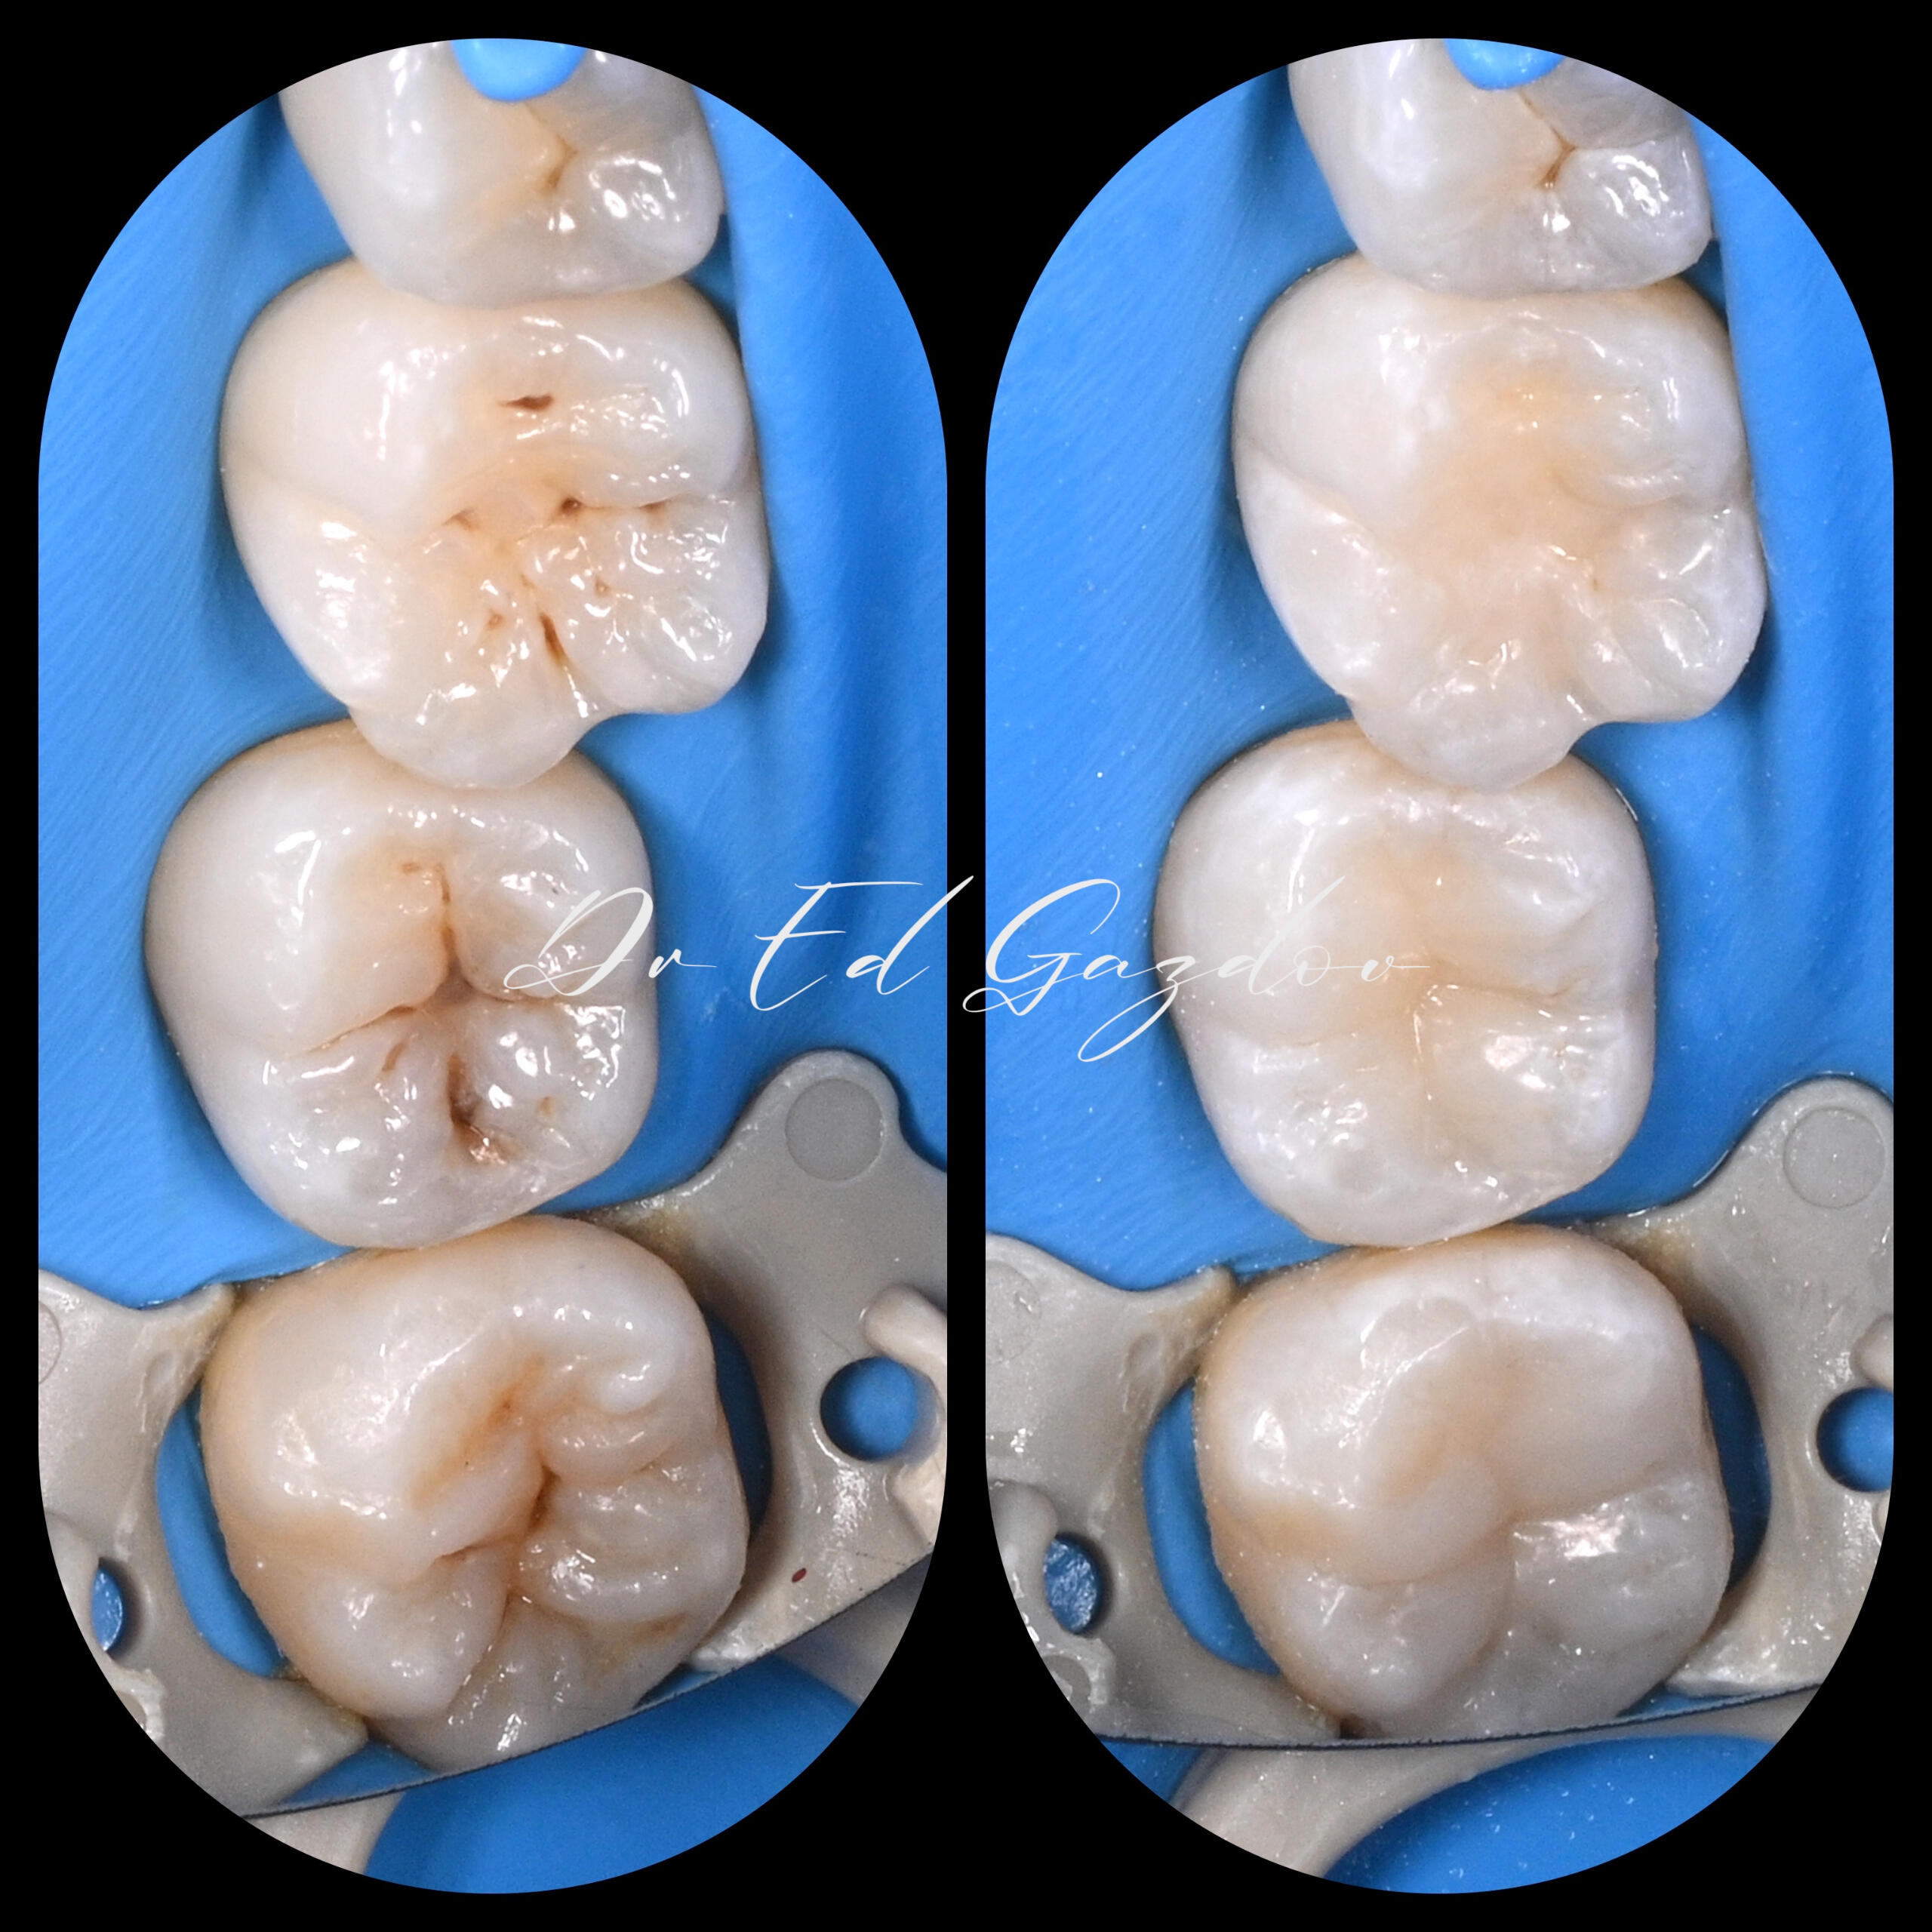

• Запазване на силно увредени зъби

• Импланти с незабавно или водено поставяне – според случая и Вашите предпочитания• Фасети, корони и мостове с минимално изпиляване и естествена визия• Пълна трансформация на усмивката, планирани дигитално и изпълнени с внимание към естетиката• Хирургично вадене на зъби, включително трудни или инфектирани случаи• Директни фотополимерни възстановявания – бързо и щадящо решение при отчупвания и леки корекции• CEREC корони и инлеи, изработени и поставени на място, в рамките на часове• Прелекуване на стари канали, корони и мостовеРаботим под увеличение, използваме rubberdam, модерни дигитални технологии и най-висок клас материали.Обясняваме ясно какво правим и защо — за да се чувствате спокойни, уверени и информирани на всяка стъпка от лечението.